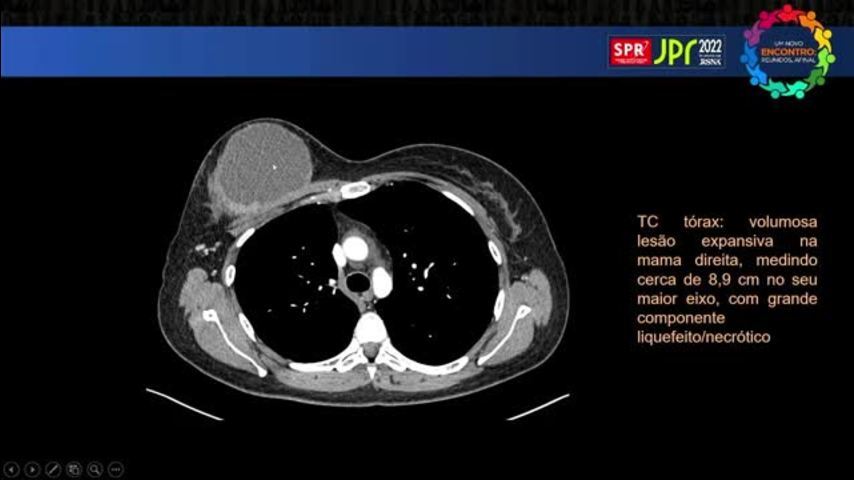

Linfoma Anaplástico de Grandes Célula...

Linfoma Anaplástico de Grandes Células Associado ao Implante - Fleury